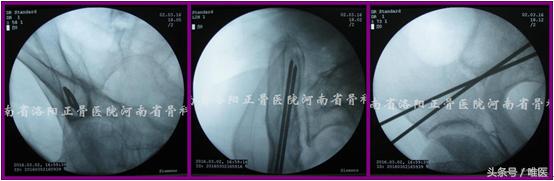

3. 置钉操作步骤

(1)确定进针点 透视出患侧骨盆Teepee像。两枚克氏针十字交叉放置于术区(AIIS尖部稍偏外侧)并调整,直至其交点正好位于Teepee像上“水滴”或“圆锥形帐篷”的中点(拟置入一枚螺钉时)或中点的稍尾端(拟置入两枚螺钉时)。应用亚甲蓝标记克氏针交点所对应的皮肤。于上述皮肤进针点做一长约1.0cm切口并钝性分离至AIIS。(图8)

图8. 确定进针点。

(2)置入导针 沿上述切口置入一枚无螺纹的空心钉导针至AIIS骨质。在骨盆Teepee像上确定针尖在“水滴”或“圆锥形帐篷”内的位置良好后将导针轻浅打入骨质,然后尽可能将导针调整成点状后再继续打入骨内(可保证导针沿安全通道的长轴行进而不会突破其周围骨质)(徒手操作时往往极难实现)。注意导针应避开安全区域的内下方以免置入过长时突入SIJ[17]。(图9)

图9. 置入导针。

(3)导针入位 如导针被成功地调整并维持成点状,则透视患侧的髂骨斜位像并在其监视下将导针打过骨折端至一定长度(避免超出髂骨后部即PSIS、PIIS骨皮质以免突入软组织内),此时导针必定位于髂窝薄弱骨质的尾端,GSN及髋臼头端。如未能将导针调整成圆点,尽管在髂骨斜位上其位置良好,仍需要追加透视患侧髂骨入口位像以确定其位于后部髂骨的内外板之间、IC之前进而避免其突入软组织及SIJ内。(图10)

图10. 导针入位。